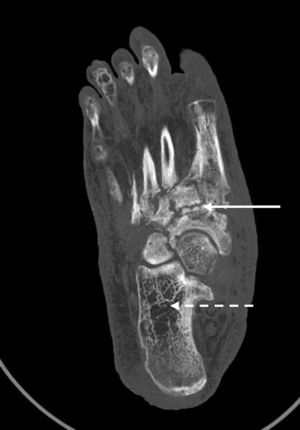

La osteoneuropatía de Charcot es una entidad potencialmente destructiva que ocurre asociada a las afecciones que causan pérdida de sensibilidad en los pies, siendo la neuropatía periférica secundaria a la diabetes mellitus la causa más común, con una incidencia entre el 0,1 y el 5%1,2. No obstante, otras condiciones patológicas podrían causar el pie de Charcot, como es la neurosífilis, la esclerosis múltiple, la poliomielitis, la deficiencia de ácido fólico y vitamina B12, la infección por VIH y el abuso crónico de alcohol entre otras1,2. Los datos publicados de prevalencia e incidencia de la enfermedad indican que a menudo no se diagnostica entre los dependientes del alcohol, con cifras que van del 0,4 al 13%, datos similares a los pacientes diabéticos1,2. La deformidad del «pie en mecedora» es su manifestación tardía y más grave1,2. Presentamos el caso de un paciente varón en su quinta década de vida, no diabético y consumidor crónico de 350g de alcohol/semana. Ha ingresado en nuestro centro por úlceras de ambas piernas. A la anamnesis ha explicado cuadro de 12 meses de evolución de aparición de edemas, úlceras y sensación ardiente de piernas, así como hinchazón progresivo del pie derecho, sin traumatismo previo. La exploración ha evidenciado úlceras supurativas y pie derecho deformado plano convexo con eritema y ulceración plantar (rocker-bottom foot o pie en mecedora). Se ha realizado tomografía computarizada (fig. 1), que ha demostrado afectación difusa con desestructuración y remodelación ósea del mesopié tarso-metatarsiana y escafo-cuneiformes (flecha blanca recta), y áreas radiolúcidas compatibles con osteopenia por desuso (flecha blanca punteada). Se ha realizado electromiografía, que ha demostrado neuropatía periférica sensorial. Ante los hallazgos clínico-epidemiológicos, radiológicos y neurológicas se ha diagnosticado de osteoneuropatía de Charcot. El síndrome de dependencia del alcohol es una enfermedad social crónica, siendo la polineuropatía periférica su complicación neurológica más frecuente, y está relacionada con deficiencias nutricionales (malabsorción de tiamina —vitamina B1—) y la neurotoxicidad directa del etanol como presumibles factores de riesgo para desarrollar el pie de Charcot. Los factores desencadenantes y la patogénesis del pie de Charcot no están claros, pero probablemente se asocia con factores mecánicos y vasculares secundarios a la neuropatía periférica sensorial y autonómica. En la fase aguda es esencial el diagnóstico diferencial con celulitis, osteomielitis o trombosis venosa profunda. El pronóstico depende de la detección precoz, y la respuesta al tratamiento depende del estadio en el momento del diagnóstico. El tratamiento inicial —como es el caso que presentamos—, además del antibiótico ajustado —en caso de infección asociada— y las curas de enfermería, consiste en la inmovilización y descarga del pie mediante yeso completo, para minimizar el edema y detener la progresión de la enfermedad. En una segunda fase, se utilizan los calzados hechos a medida3,4. Si fracasa, en los pies con deformidad severa, se puede practicar una cirugía —para lograr un pie plantígrado y evitar que las exostosis provoquen presión en la piel y por lo tanto úlceras, una cirugía de tendones para restaurar el equilibrio muscular o la reconstrucción electiva para dejar un pie funcional y prevenir la amputación—3,4, que, en nuestro caso, ha sido rechazada por el propio paciente.